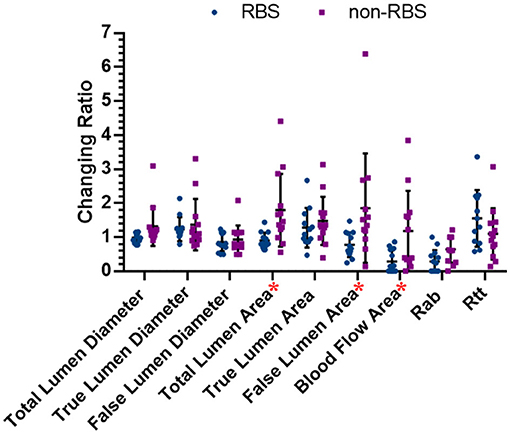

Figure 5 shows the comparing results of all the changing ratios between the latest follow-up and preoperative data in two groups. The changing ratio between RBS and paired non-RBS patients in total lumen area (dif = −0.89, p = 0.007), FL area (dif = −1.07, p = 0.028), and blood flow area (dif = −0.90, p = 0.015) shows significant difference, which means patients receving RBS are more likely to decrise the areas of total aortic lumen, true aortic lumen, and blood flow in the FL than those in non-RBS. As for the changing ratio of other items, although the results are not statistically significant, all the changing ratios in RBS group have the positive trend than those in non-RBS group.

Figure 5. Changing ratios in both RBS and non-RBS groups. Changing ratio: the latest data/preoperative data; * represents there is significant difference between two groups (p < 0.05).